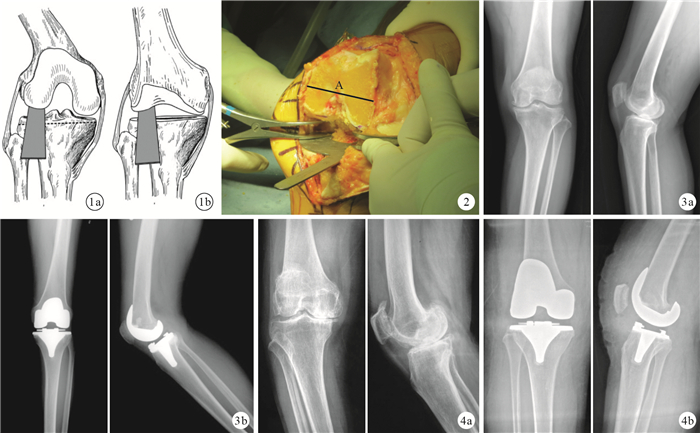

試驗組:截骨順序依次為脛骨平臺、股骨遠端、股骨遠端四合一截骨。屈膝90°內翻膝關節(“4” 字試驗),于外側脛股關節間隙插入間隙測量試模確定其間隙(flexion gap,F);根據測量結果按照以下公式計算脛骨外側平臺所需截骨量,擬完成屈曲間隙(22?mm)-股骨假體后髁厚度(9 mm)-外側脛股關節屈曲間隙(F?mm)。安裝脛骨截骨測量器,根據計算得出的截骨量,調整截骨模塊高度并完成脛骨平臺截骨(圖 1?a)。再次于屈膝90°插入間隙測量試模,保證脛骨平臺截骨后外側脛股關節間隙為13 mm。膝關節伸直,于外側脛股關節間隙插入間隙測量試模確定其間隙(extension gap,E);根據測量結果按照以下公式計算股骨遠端截骨量,擬完成伸直間隙(20 mm)-外側脛股關節伸直間隙(E mm),根據計算結果完成股骨遠端截骨(圖 1?b)。插入膝關節間隙試模(20 mm;Biome公司,美國),判斷伸直間隙,內側軟組織松解完成伸膝間隙平衡。屈膝90°并采用間隙平衡技術確定股骨遠端外旋角度及四合一截骨;股骨外旋截骨角度由內外側脛股關節間隙等張撐開后脛骨平臺截骨面的平行線確定,同時通過股骨外科外上髁軸進行校對 (圖 2)。

術后6周兩組ATFA、髕骨傾斜角及關節線高度比較,差異均無統計學意義(P > 0.05);試驗組PCO明顯小于對照組,比較差異有統計學意義(t=2.789,P=0.007)。組內比較,對照組術后6周ATFA、髕骨傾斜角、關節線高度及PCO與術前比較,差異均有統計學意義(P < 0.05);試驗組ATFA及髕骨傾斜角手術前后差異有統計學意義(P < 0.05),但關節線高度及PCO手術前后差異無統計學意義(P > 0.05)。見表 2及圖 3、4。X線片檢查,隨訪期間假體無松動、下沉等情況發生。